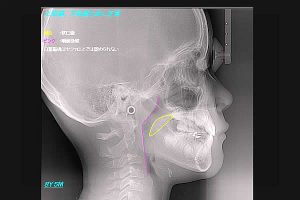

(図5)

鼻閉のため口呼吸をしている男児のX線側貌セファロ写真

鼻腔が曇っているから口呼吸を余儀なくされる。そのため直接外気が当たり、口蓋扁桃が腫脹している様子が見てとれる。青の部分であるそこで著しく気道が狭窄している。そうか!口呼吸をしている子ども達が、意欲に欠けるのは酸素の供給量が少ないためではないか・・・。扁桃腺の腫脹のため、咽頭部では酸素の通過障害が起きているに違いない。これでは、勉強どころではないな・・・。